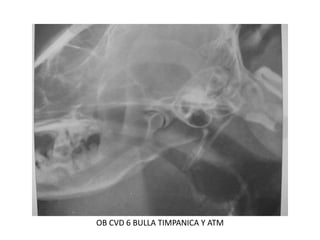

Posición lateral

oblicua para observar

bulla timpanica y art.

temporomandibular

OB CVD 6 BULLA TIMPANICA Y ATM

OB CVD 7 BULLA TIMPANICA Y ATM 2